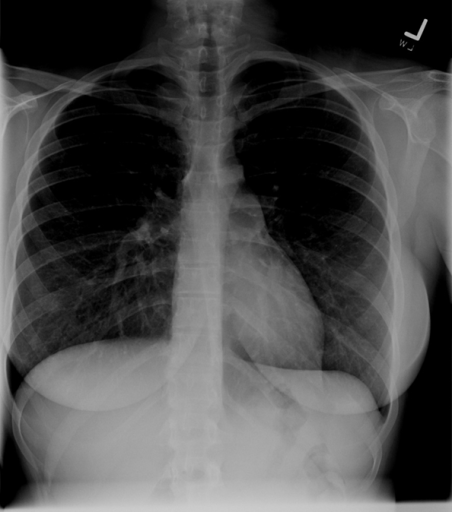

Inspiration

Deeper inspirations show more lung and result in better overall images with less haziness at the lung bases and less enlargement of the heart and mediastinum. A good inspiration on a PA CXR shows at least 9 posterior ribs.

The following films were of the same patient and taken using the same AP projection. The image on the left is a poor inspiratory effort (ribs 1-6), while in the film on the right, the patient achieved a much deeper inspiration on the bottom xray (ribs 1-10).

Poor Inspiratory Effort Good Inspiratory Effort